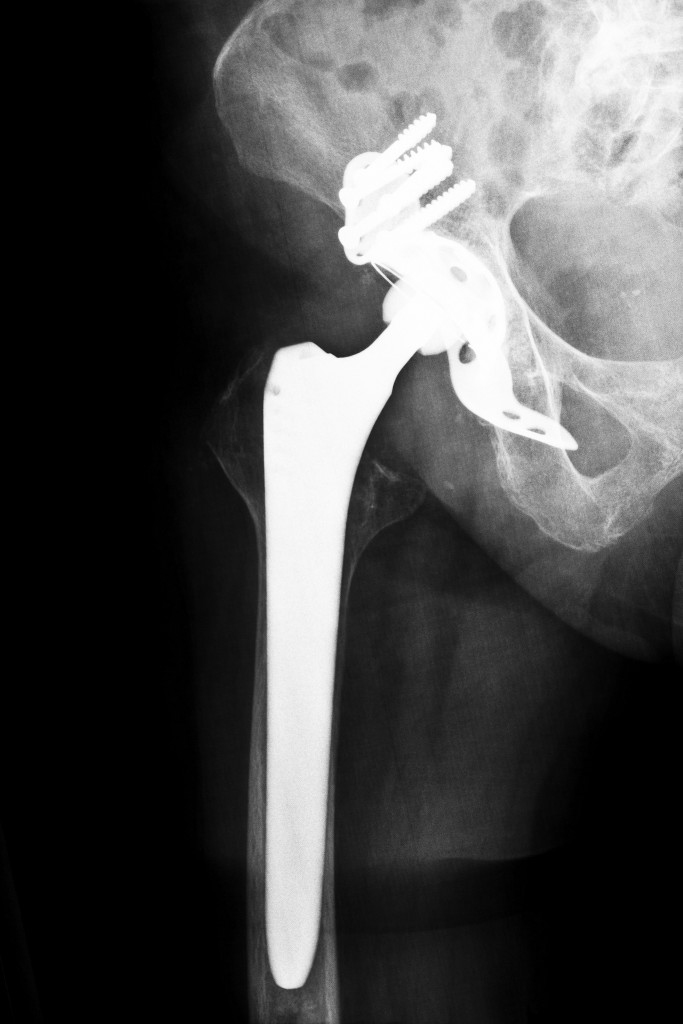

From www.wjgnet.com

Offtheshelf 3D printed titanium cups in primary total hip arthroplasty Titanium Hip Replacement Side Effects Titanium is a common material used in hip implant devices and can result in. In the months after her debridement and prosthesis revision, the patient continued. Having a metal allergy or sensitivity doesn't mean getting a metal implant like a surgical screw, plate, or joint replacement is entirely off limits or that the body will reject it. See metallosis symptoms. Titanium Hip Replacement Side Effects.